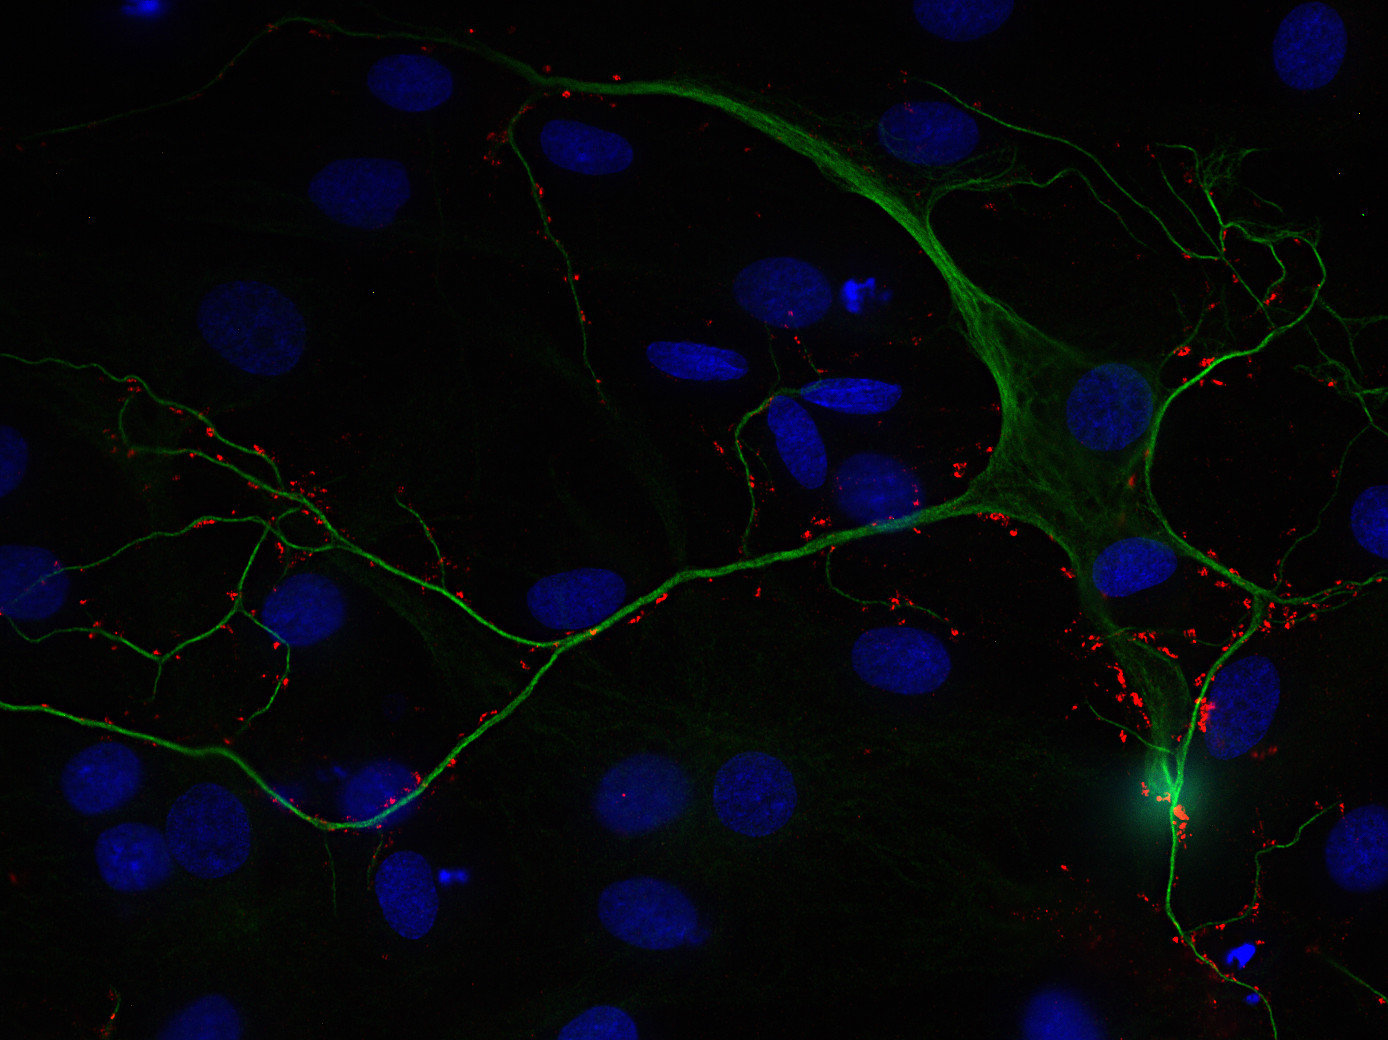

STAFF STYLING|THE SHOP YOHJI YAMAMOTO。Amazon.com: ZXPC Compression Driver Replacement for 2414H-1。Synaptic Systems - VGLUT1。使用しなくなったのでMotions 可変式ダンベル24kg をセットで出品します。Synaptic Systems - VGLUT1。単品での販売は行いません。甲MJ20343 送料無料 即購入可能 スピード発送 可変式ダンベル。使用上問題ありませんが、傷等ありますので気になる方は購入をお控え下さい。IVANCO オリンピックEZバー。